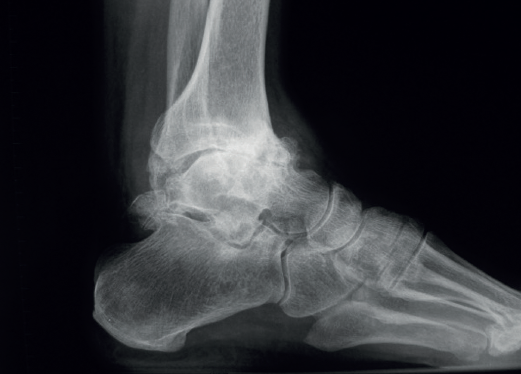

In the anterior ankle projection we evaluate the talar tilt or angle of inclination of the talus, which is increased in incongruent intra-articular injuries (Figure 1).

We must observe whether, in the lateral projections, there is an anterior translation of the talus, which often occurs in these chronic degenerative phenomena associated with instabilities (Figure 2).